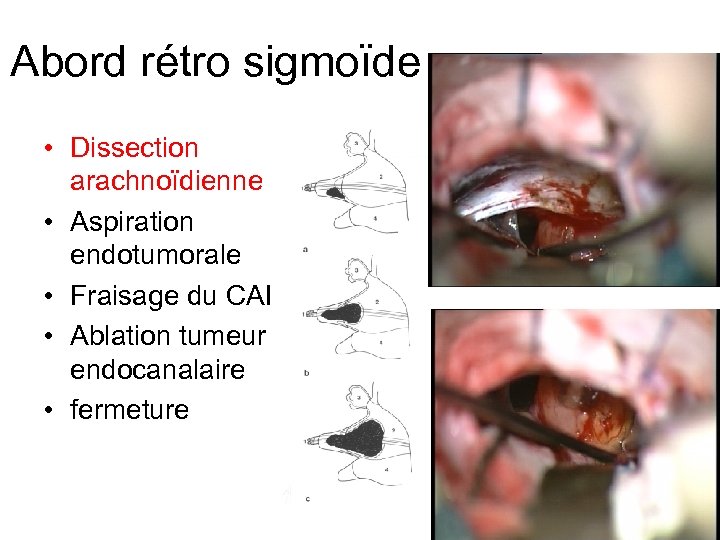

Abord rétro sigmoïde • Dissection arachnoïdienne • Aspiration endotumorale • Fraisage du CAI • Ablation tumeur endocanalaire • fermeture

Abord rétro sigmoïde • Dissection arachnoïdienne • Aspiration endotumorale • Fraisage du CAI • Ablation tumeur endocanalaire • fermeture

Abord rétro sigmoïde • Dissection arachnoïdienne • Aspiration endotumorale • Fraisage du CAI • Ablation tumeur endocanalaire • fermeture

Abord rétro sigmoïde • Dissection arachnoïdienne • Aspiration endotumorale • Fraisage du CAI • Ablation tumeur endocanalaire • fermeture

Abord rétro sigmoïde • Dissection arachnoïdienne • Aspiration endotumorale • Fraisage du CAI • Ablation tumeur endocanalaire • Stimulateur • Fermeture +++ (graisse)

Abord rétro sigmoïde • Dissection arachnoïdienne • Aspiration endotumorale • Fraisage du CAI • Ablation tumeur endocanalaire • Stimulateur • Fermeture +++ (graisse)